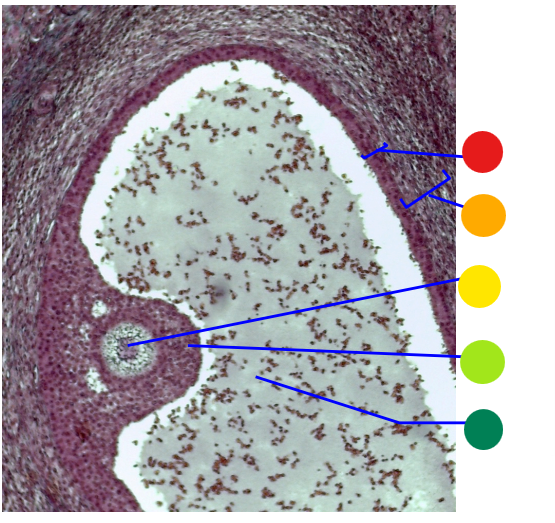

red

primary oocyte

orange

zona pellucida

yellow

granulosa cells

light green

developing thecal cells

What is this

secondary follicle